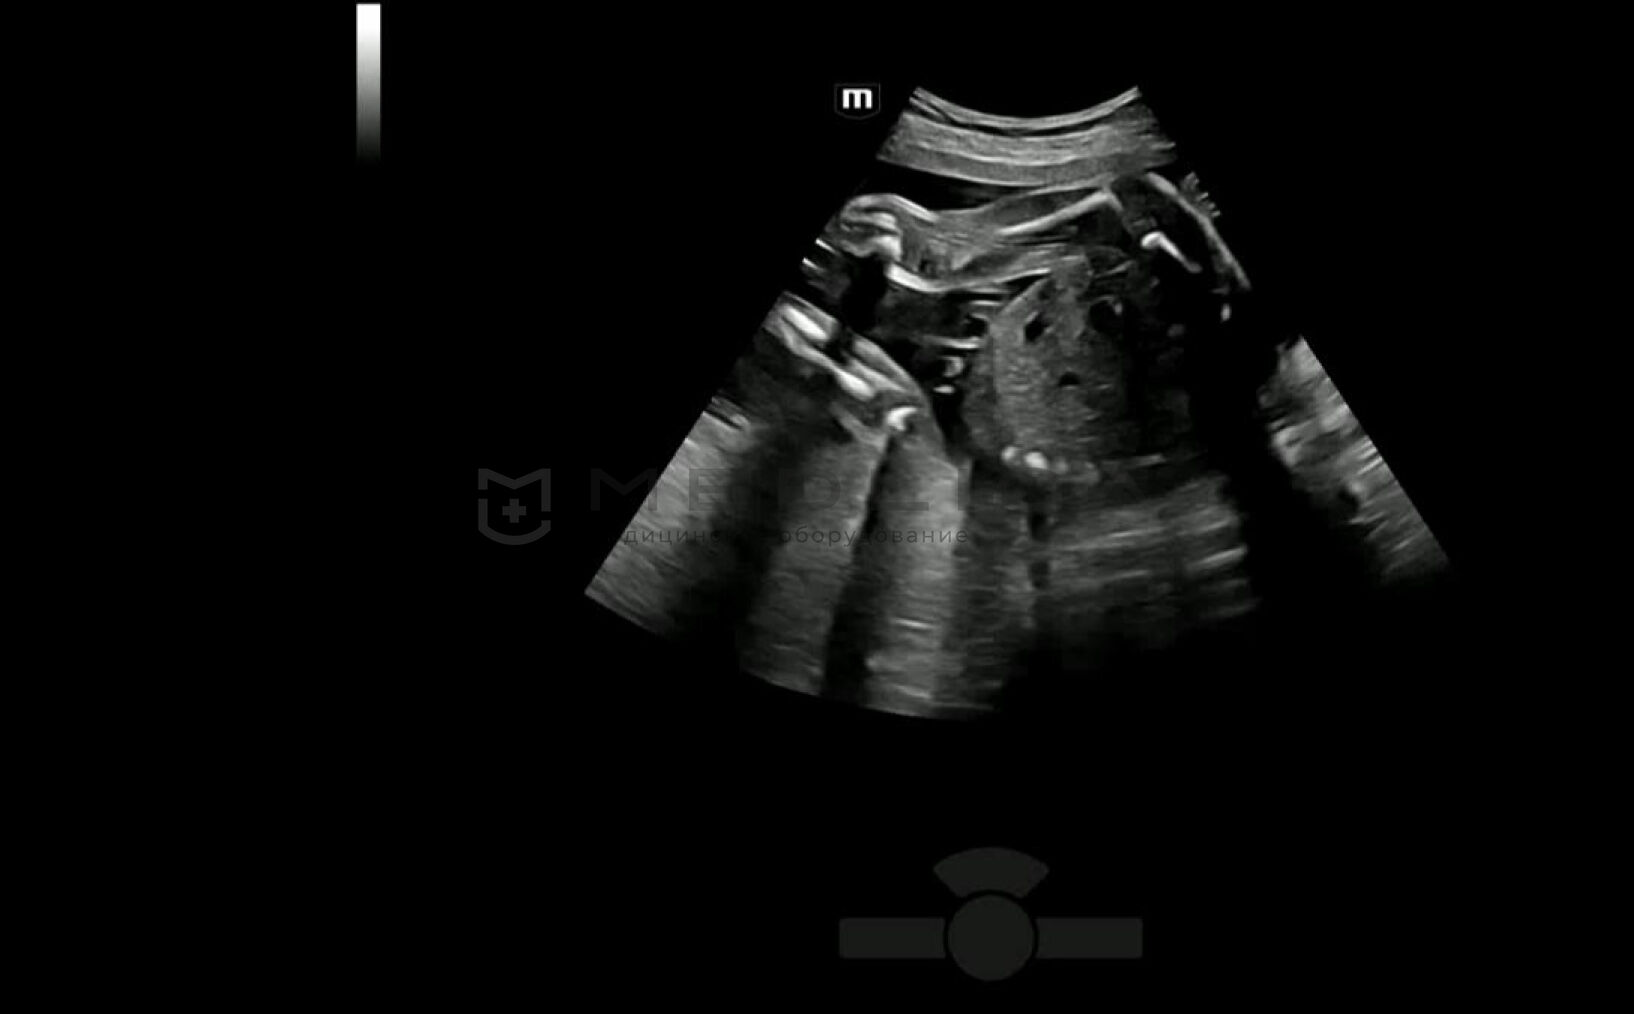

Легкое получение 3D изображения костей

- Автоматическое распознавание костей конечностей плода

- Автоматическая подстройка зоны интереса и положения до оптимального

- Автоматический рендеринг изображения